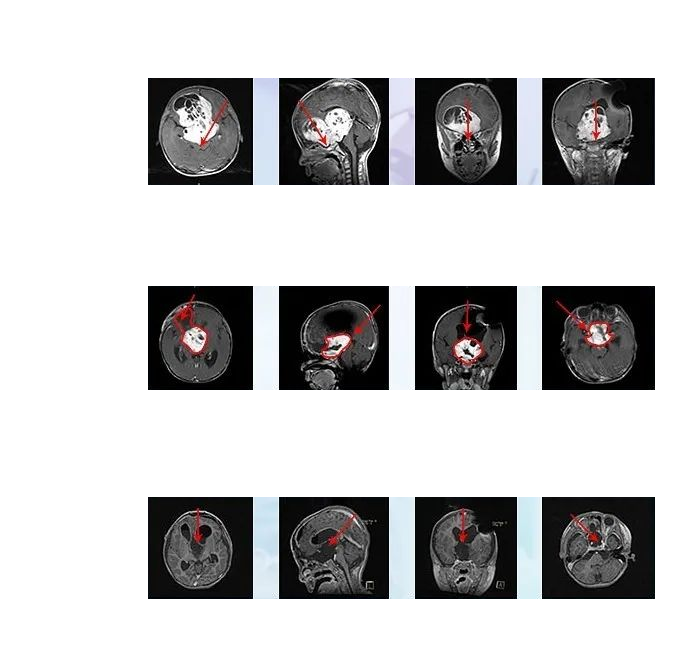

目前,大多数视神经胶质瘤是无症状的,因此要么在筛查评估中被发现,要么在为其他目的进行成像时偶然被发现。含钆和不含钆的脑和眼眶的磁共振成像是优选的放射成像方式。视神经胶质瘤本质上是典型的管状或梭形,在T1像上呈等信号,在T2像上呈等或高信号。2鉴于与活组织检查相关的视力丧失的,24很少需要手术证实,仅根据影像学特征就可以做出诊断。

病情回顾:2018年7月,年仅5岁的小冬患较大视神经胶质瘤,肿瘤严重压迫视神经等重要功能神经和脑组织,眼睛几乎没有光感,父母为他访遍国内神经外科医院,均表示这个位置无法手术,或者手术风险较大但是切除率很低,不建议治疗。

看着孩子病情一天天恶化,家长心急如焚,经过多方打探才找到INC神经外科医生集团,并在INC团队的帮助下联系到国际颅底手术教授巴特朗菲教授进行国际远程咨询。巴教授详细诊断小冬病情后表示,尽管视神经被肿瘤浸润包裹,但还是有很大机会切除肿瘤,且手术不会导致失明等症状。父母得到这样的咨询回复,立即决定带小冬赴德国找巴教授手术。

治疗过程:巴教授根据肿瘤具体位置、大小和形态制定个体化手术方案,通过额骨颅骨开颅术和大脑半球间穹窿入路,在神经电生理监测护航下实现近全切肿瘤,术中无新发功能神经损伤,术后无新发长期性并发症。术后两周出院,小冬视力明显好转,可自行站立、短距离行走。

胶质瘤压迫几乎失明,赴德手术全切保留视力,术后1年随访,原本已经失明的小冬视力渐渐恢复了,术后3年半随访,肿瘤全切并没有复发,视力较前明显好转